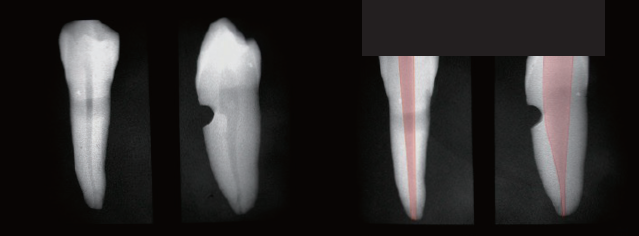

(図1)に示したような小臼歯の場合、近遠心的な形態は歯髄腔の太さも細く、湾曲している場合は器具操作が難しく、根管充填材が根尖まで到達し難いため、それを解消するために便宜的に形態修正する必要がある。そのような形態を付与することを「修正形成」と考える。また、頬舌的には歯根の約半分の太さを有する歯髄腔に対して、意図的に切削器具を歯髄腔内壁に押し当てて削除する必要があり、その処置が不十分になると起炎性因子の取り残しが起き、予後に影響が出る。このような太い根管において器具操作を行うことで、根管内の起炎物質を的確に除去できるような形態を付与することを「予防形成」と考える。この、(図1)の歯の根管拡大・形成を行う場合、咬頭を残した髄室開拡を行うと頬側の髄腔は咬頭頂よりも頬側に広がっているため、切削器具を意識して傾けて操作しなければならない。

(図1) 歯髄腔内壁形成の必要条件

近遠心方向、頬舌方向それぞれ角度の異なるテーパーを立体的に組み合わせてフレアー形成を行う